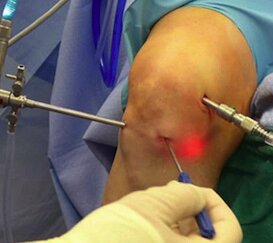

Arthroscopic (Keyhole) Surgery

Minimally invasive arthroscopic procedures enable treatment of ligament injuries, meniscus tears, shoulder instability, and rotator cuff problems through small incisions with faster recovery.

Arthroscopic Knee Surgery

ACL & PCL Reconstruction Arthroscopic ligament

Meniscus Repair & Cartilage Procedures

Shoulder Arthroscopy